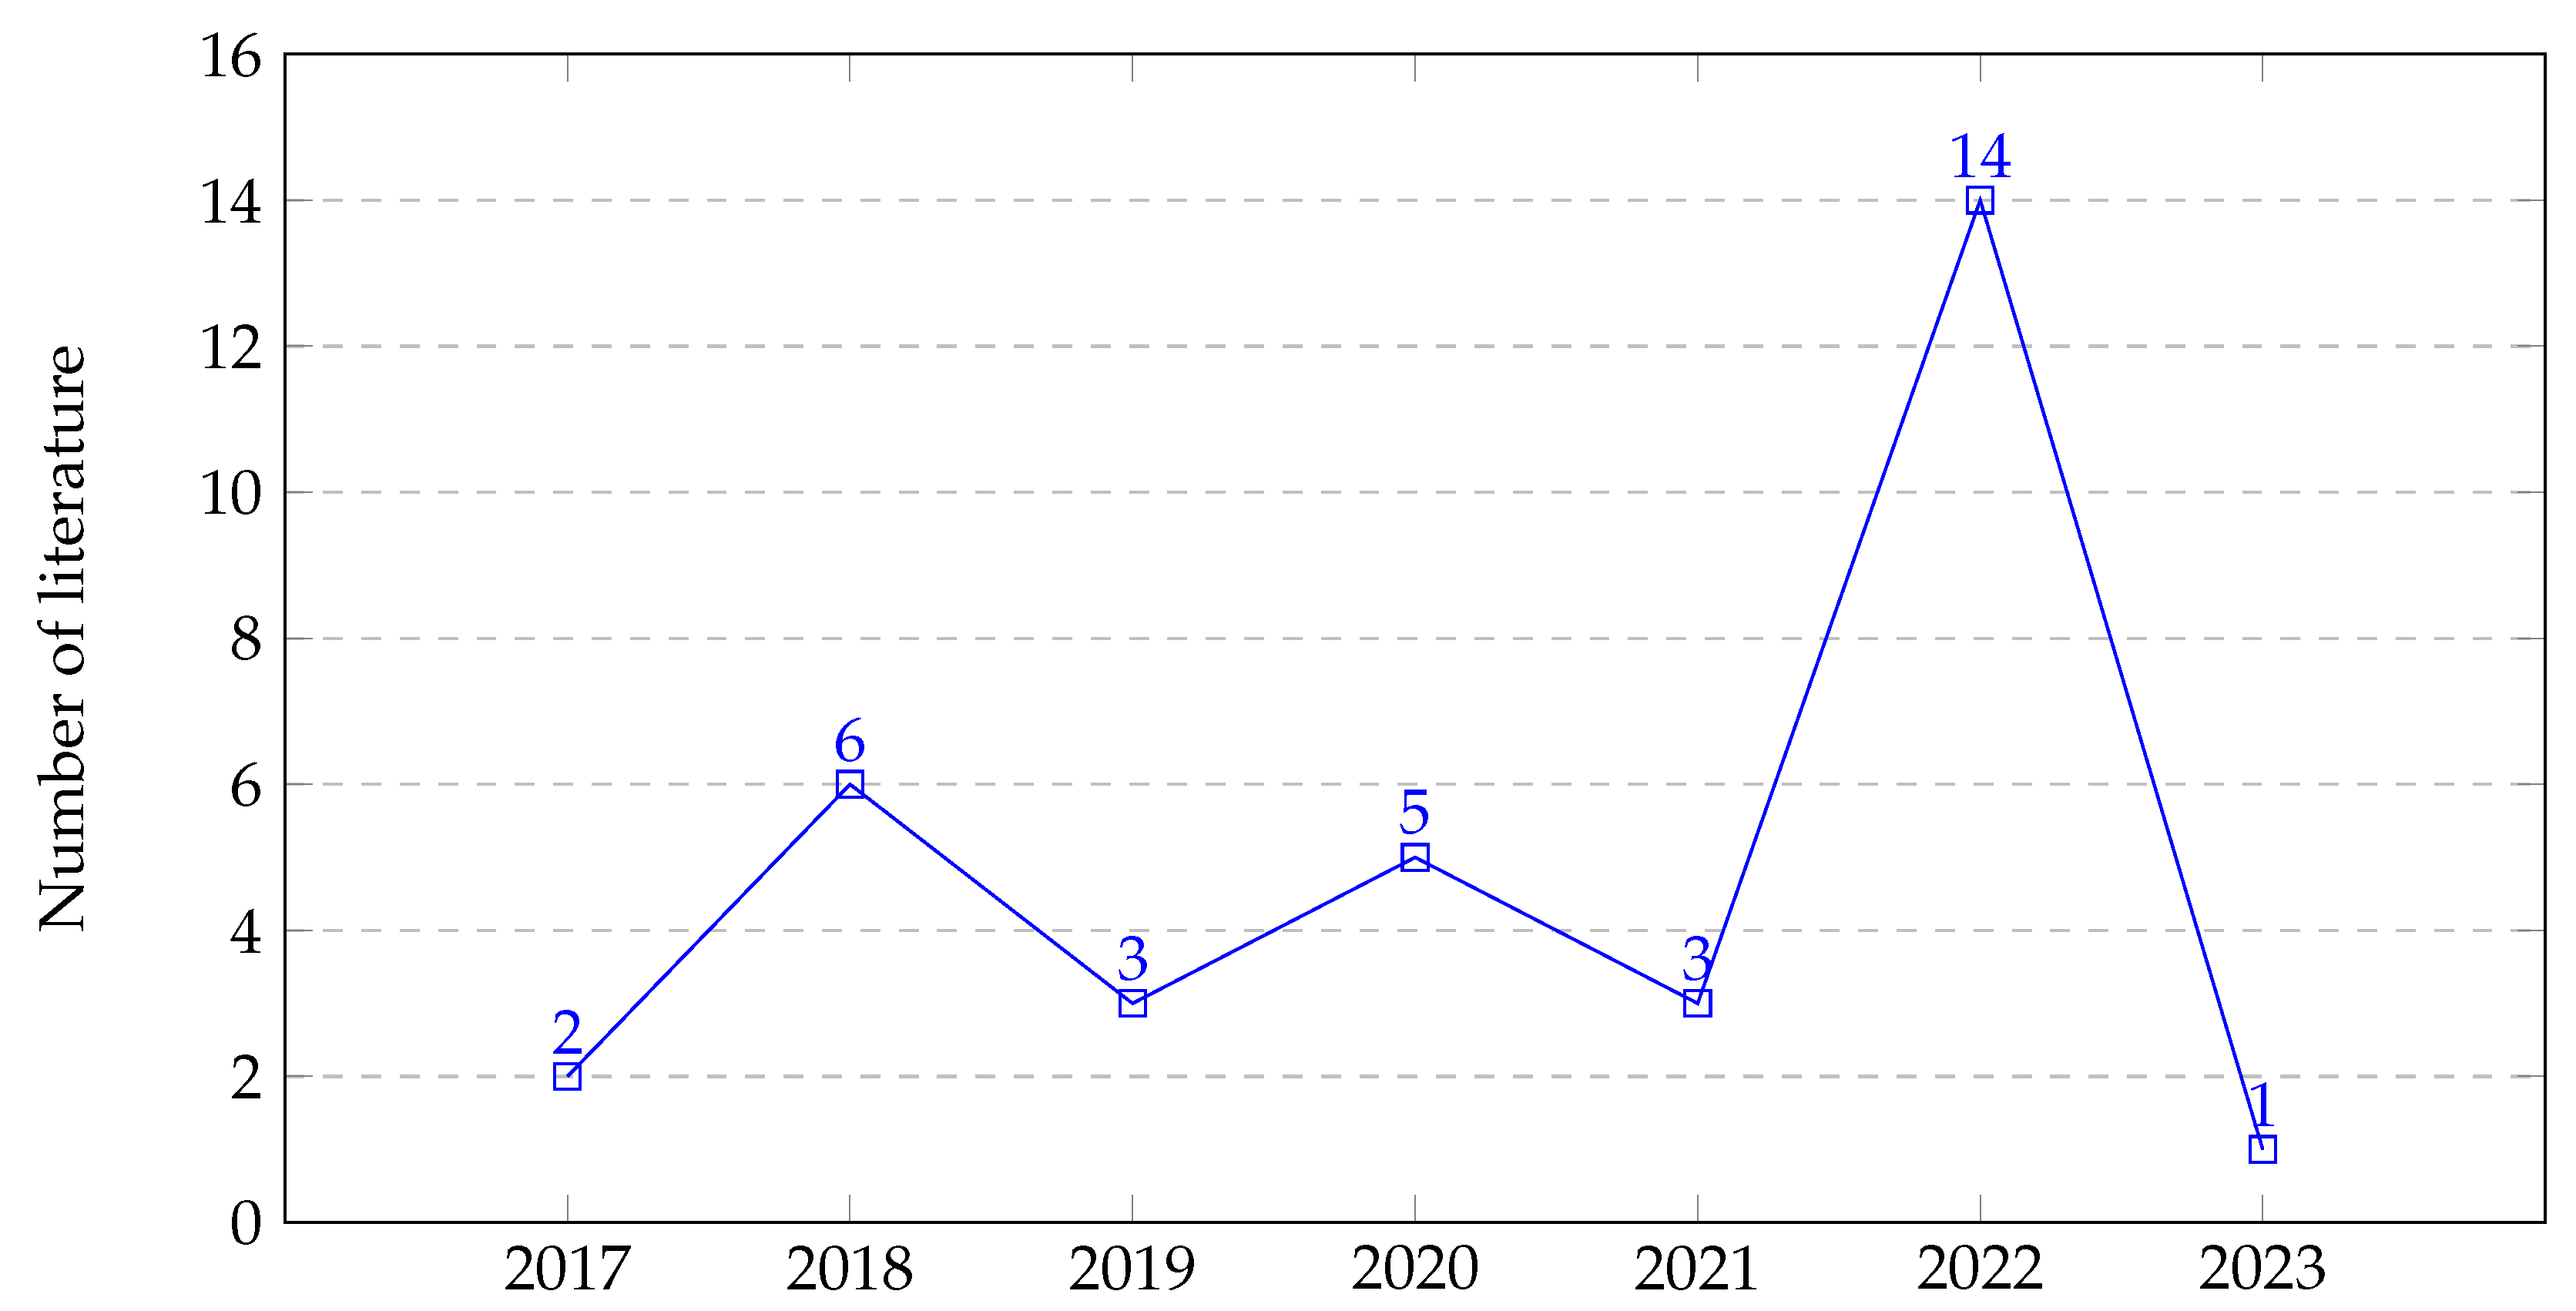

3. Methodology

3.2. Search Strategies